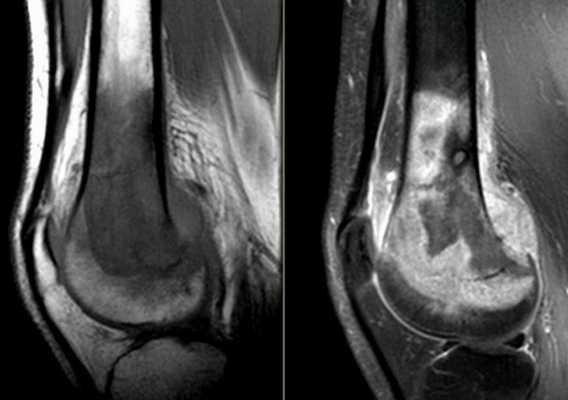

МРТ плечевого сустава. Т2-взвешенная корональная МРТ. Разрыв вращательной манжеты. Цветовая обработка изображения.

МРТ плечевого сустава. Корональные Т1-взвешенные МРТ. Переломы Хилла-Сакса и Банкарта.

Разрыв вращательной манжеты - также характерное повреждение области плеча - может быть связан как с травмой, так и дегенеративными процессами. Разрывы вращательной манжеты бывают полные и неполные. Кроме того, по МРТ плечевого сустава выделяют 3 градации, в основе которых лежит не только изменение сигнала на Т2-зависимых томограммах, но и морфологические изменения сухожилия.

МРТ. Корональная Т2-зависимая томограмма с подавлением сигнала от жира. Полный разрыв сухожилия надостной мышцы.

МРТ плечевого сустава с подавлением сигнала от жира. Т2-взвешенная корональная МРТ. Перелом большого бугорка (стрелка).

При МРТ плечевого сустава косвенным признаком разрыва вращательной манжеты служит высокий сигнал на Т2-взвешенных от поверхности сустава до субакромиальной (субдельтовидной) сумки. Частичные разрывы чаще всего по передней поверхности сухожилия м.supraspinatus, реже примыкая к большой бугристости или сухожилия м. infraspinatus.

МРТ плечевого сустава. Т2-взвешенная корональная МРТ. Субакромиальное скопление жидкости - косвенный признак разрыва вращательной манжеты.

МРТ плечевого сустава. Т1-взвешенная корональная МРТ. Частичный разрыв вращательной манжеты.

МРТ плечевого сустава. Т2-взвешенная корональная МРТ. Передний разрыв вращательной манжеты